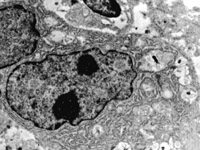

5-2-5 傷后第5天,膠原纖維相互融合,其間的細胞已崩解  TEM×6000